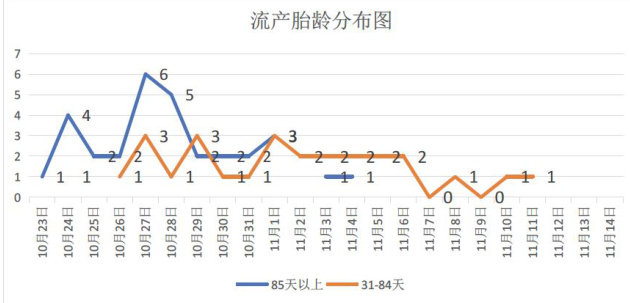

实践案例 | 浙江省某大型规模猪场蓝耳病引起流产的诊治案例分析

实践案例 | 浙江省某大型规模猪场蓝耳病引起流产的诊治案例分析